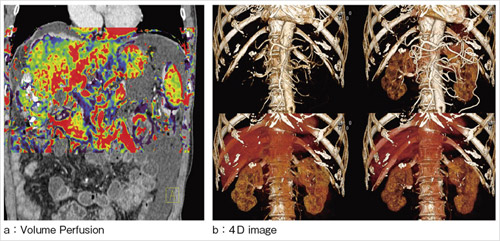

図3 Adaptive 4D Spiral によるVolume Perfusionと4D image |

シーメンスがマルチスライスCTの最新機種(図1)に搭載した“Adaptive 4D Spiral”は,これらの制限を解消する新しい撮影技術である(図2,3)。Adaptive 4D Spiralは,寝台のスムーズな加減速を行う連続往復Spiral Scanによって1〜1.5秒間隔で途切れのない経時的データを取得し,パーフュージョン等の解析,4D Imagingが可能である。検査目的に応じ,撮影間隔や途中休止なども自由に調整できる。撮影中はリアルタイムに線量の最適化を行う。

さらに時間軸での処理によって,コントラストを保ちつつSNRを改善する“4D Noise Reduction”を新たに開発した。両者の併用により,線量最適化を行わない場合と比較すると,約50%の被ばく低減が可能である。

カバレッジは「SOMATOM Definition AS+」では270mmである。プラナー像での拡大率を考慮すると,体軸方向12インチのFPDに匹敵し,腹部血管造影を代替するために十分なカバレッジを確保している。さらに「SOMATOM Definition Flash」では480mmものカバレッジを有し,腹部大動脈瘤など,より広範な病変へも対応可能である。

Adaptive 4D Spiralが実現した真のOne Organ Imagingによって画像診断に新たな評価軸を提供する。